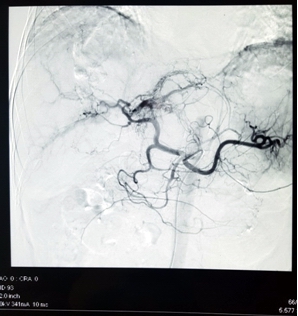

Ảnh 2: Hình ảnh động mạch thân tạng chụp bằng máy chụp mạch số hóa xóa nền: động mạch gan trái và phải còn đang có dấu hiệu chảy máu ra ngoài gan.

Ca phẫu thuật diễn ra trong khoảng 30 phút. Sau khi nút tắc động mạch mạch gan, huyết động của bệnh nhân ổn định ngay. Huyết áp tăng lên 110/70 mmHg, mạch đo được 100 lần/phút. Theo dõi sau 1 tuần, mạch và huyết áp đều ổn định, chụp cắt lớp vi tính kiểm tra lại thấy động mạch gan trái và phải tắc hoàn toàn, khối u không còn tăng sinh mạch, không còn dấu hiệu chảy máu ra ngoài khối u, lượng máu tụ trong ổ bụng đã giảm 50%.